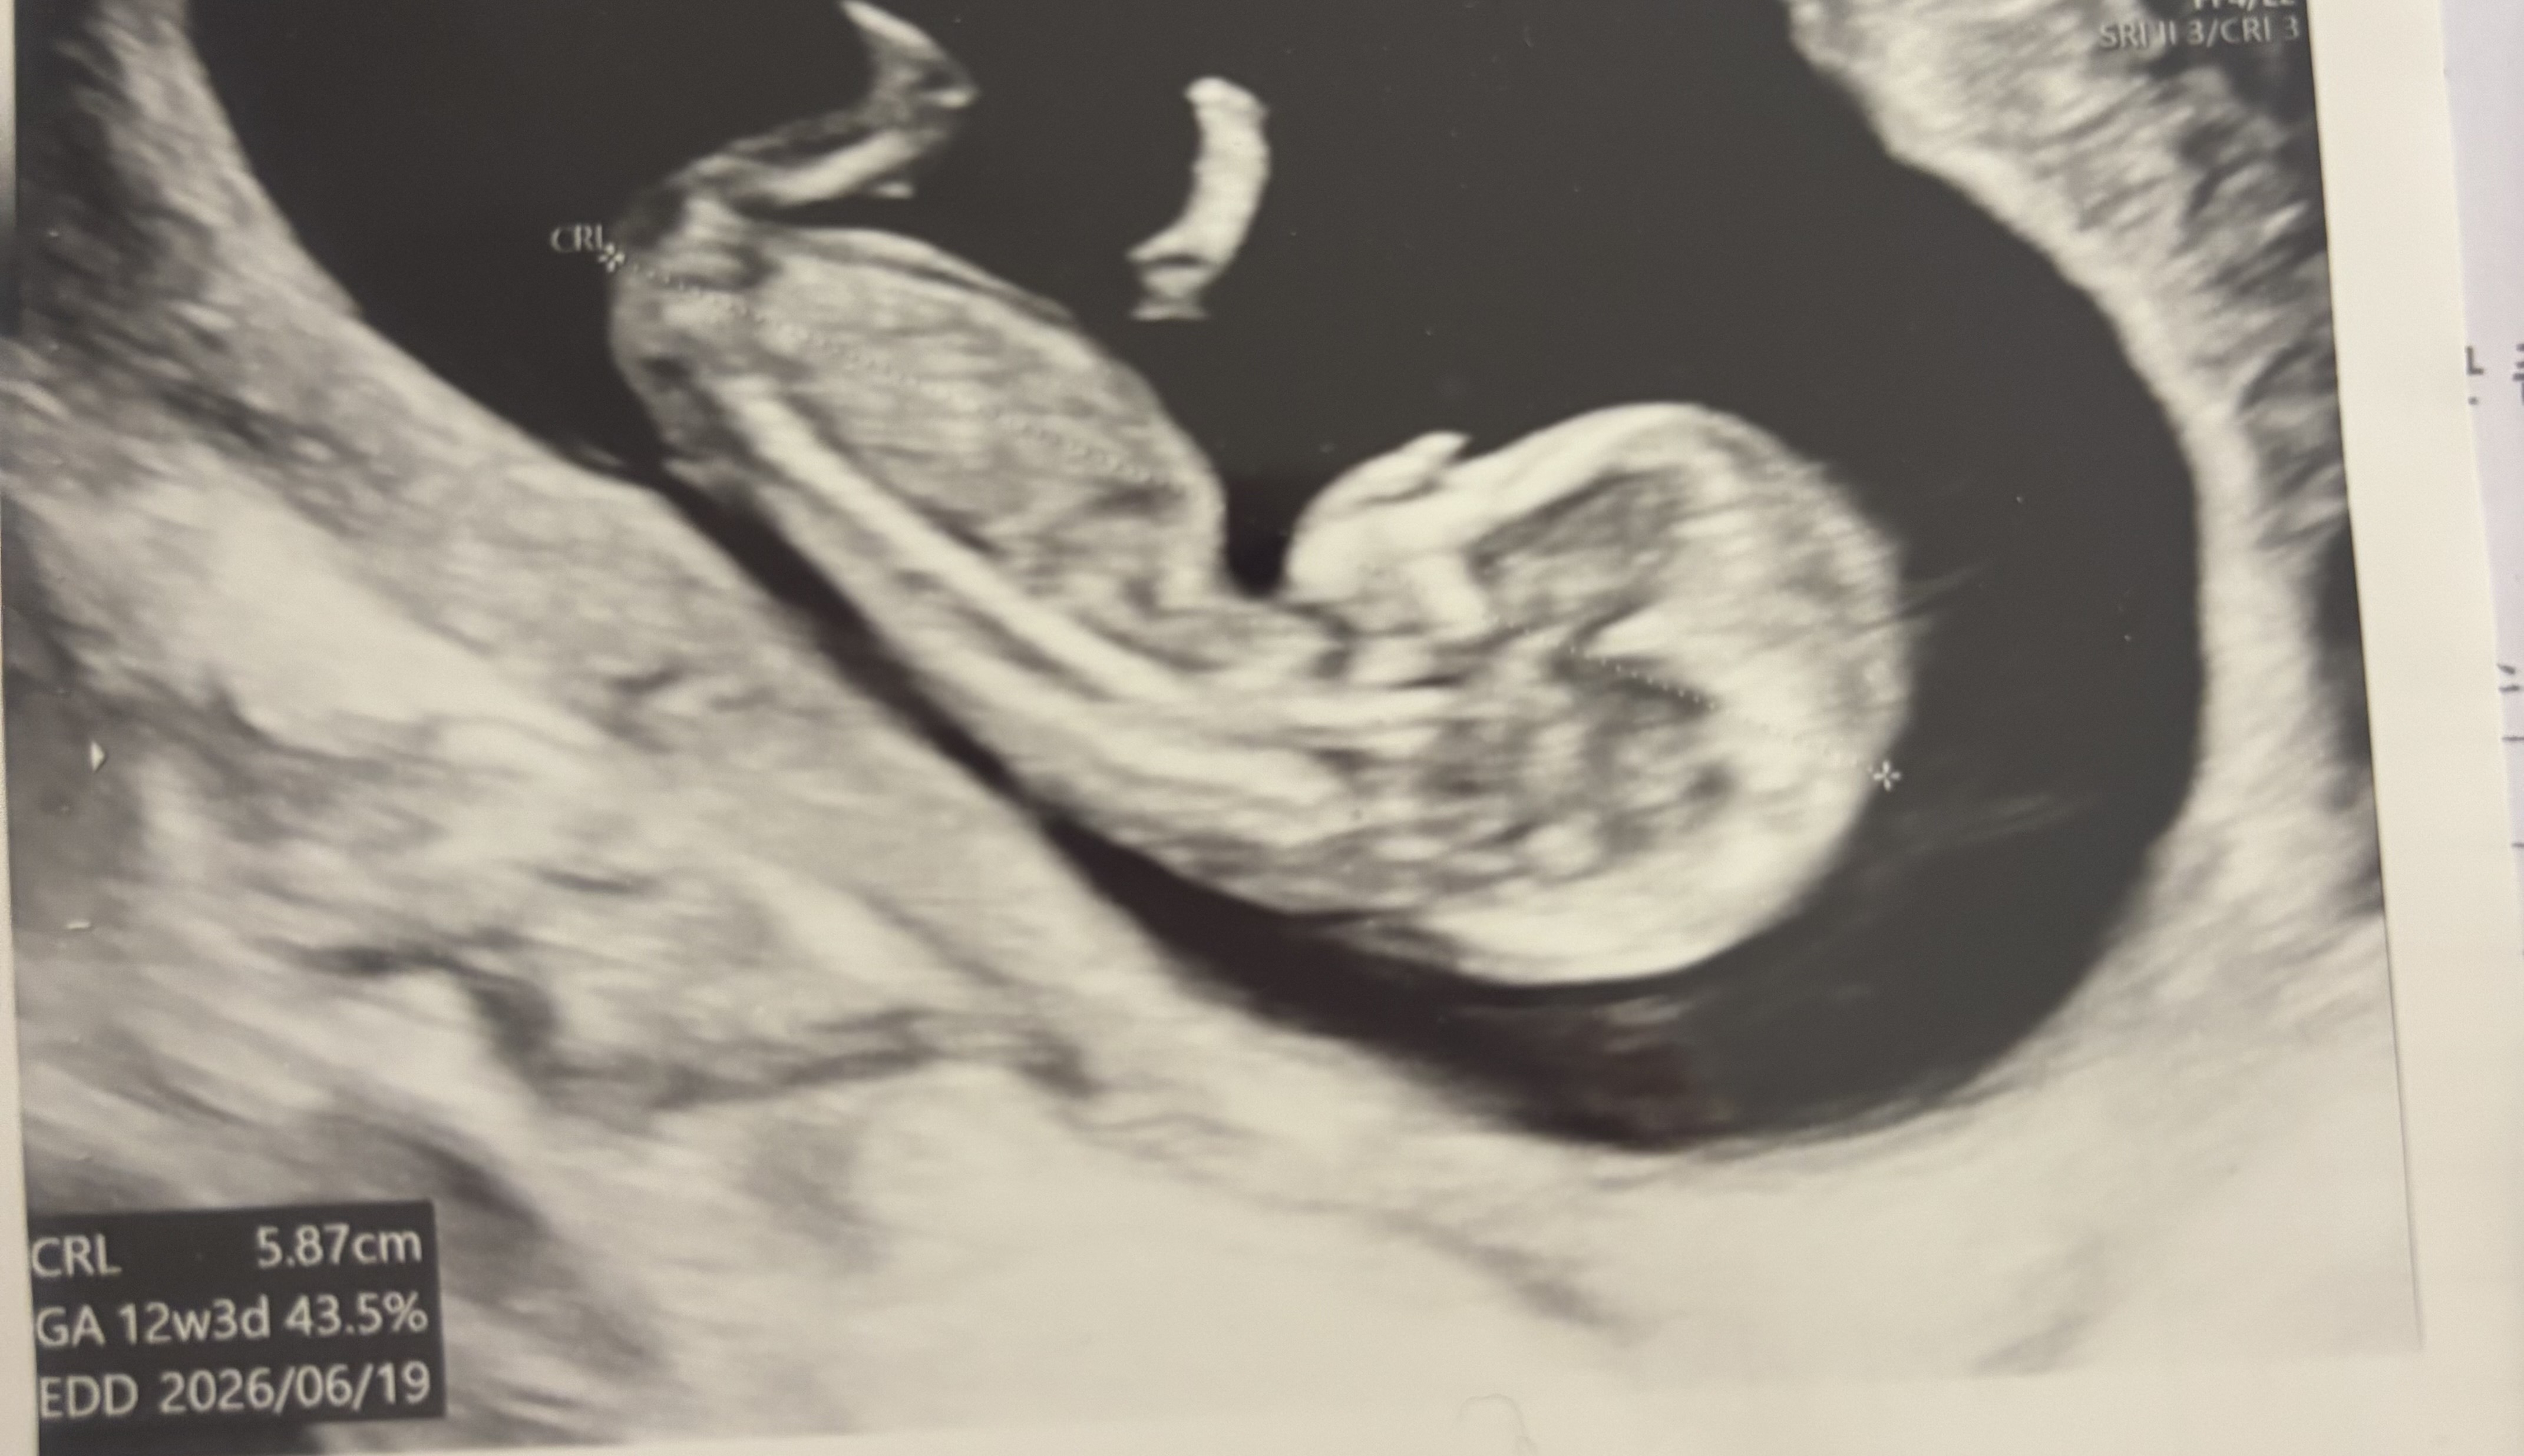

12주 3일차 초음파 각도 궁금합니다!!